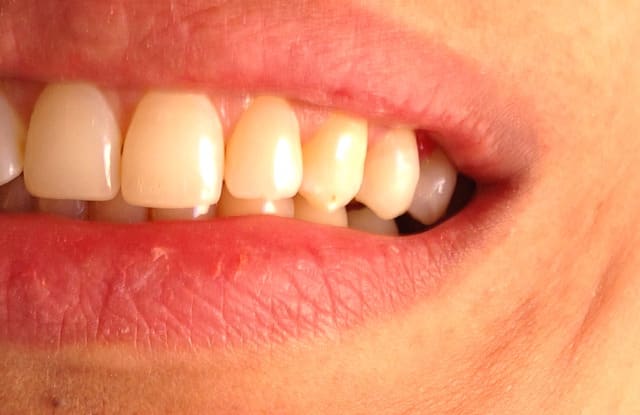

Alors comment traiteriez vous cette 24 asymptotique, qui présente un enorme délabrement sous gingival , notez que l'émail n'est plus soutenu par la dentine à aucun endroit ?

1ère séance remontées de la marche distale au compo flow + compo de restauration / réalisation d'un IDS , le tout sous digue bien sur (voir radio jointe , désolé à l'envers))

Je vous met les photos de la pose de ce matin, par contre désolé pour les puristes , mais photos faites avec un iphone....

Voici les photos toutes fraiches de ce matin.

Vos critiques sont bien sur les bienvenues je dois encore beaucoup m'améliorer sur les prises de teintes, et je m'y attelle en ce moment,, par contre en ce qui concerne la pérennité de la restauration…..ma patiente a sa dent bien vivante, aucun joint sous gingival , possibilité de réaliser une endo dans le futur sans détruire la restauration existante si besoin, possibilité re refaire un onlay dans quelques années si ça casse, toujours sur dent vivante…. bref la liste des avantages est très longue par rapport au classique endo-IC-CCM.